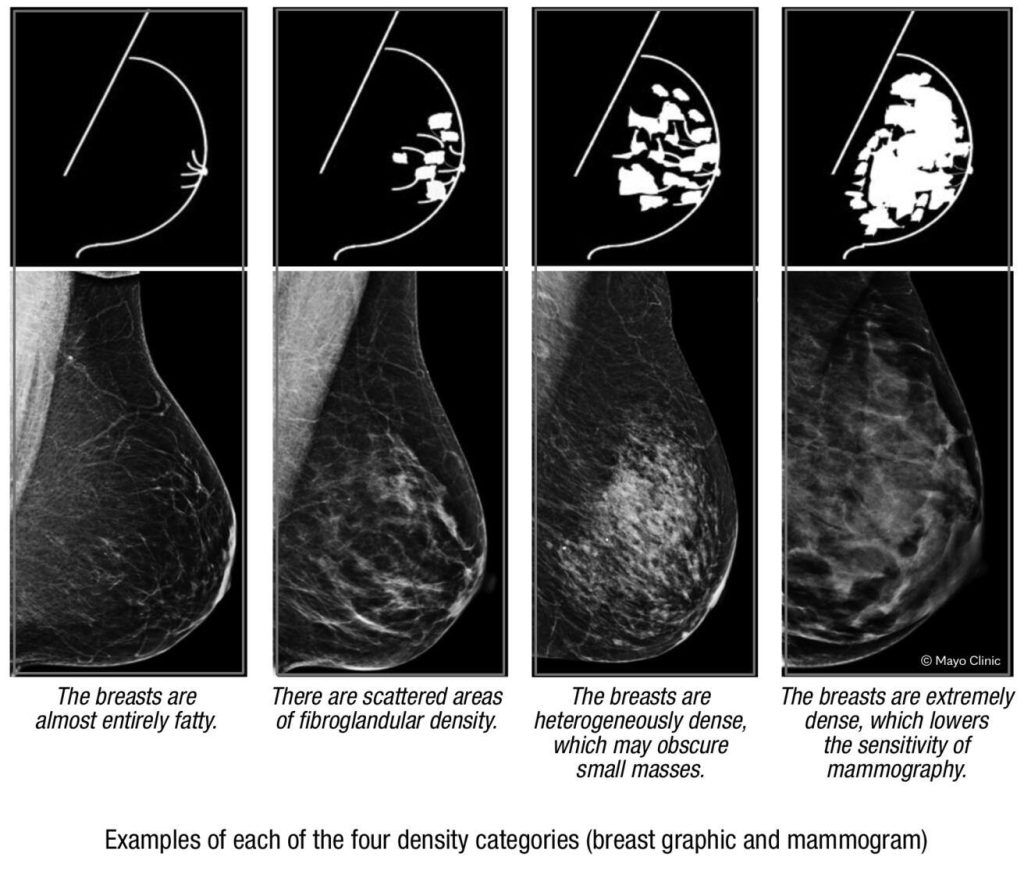

The radiologist who analyzes your mammogram determines the ratio of nondense to dense tissue and assigns a level of breast density. These levels are determined by results from the Breast Imaging Reporting and Data System from the American College of Radiology.

The levels of density are designated by letters:

- A. Breasts are almost entirely composed of fat. About 10% of women have this result.

- B. Scattered areas of density, but most breast tissue is nondense. About 40% of women have this result.

- C. Heterogeneously dense indicates some areas of nondense tissue, but most breast tissue is dense. About 40% of women have this result.

- D. Extremely dense indicates that nearly all breast tissue is dense. About 10% of women have this result.

Nondense breast tissue typically appears dark and transparent on a mammogram. In contrast, dense breast tissue appears as a solid white area, which makes it difficult to see through.